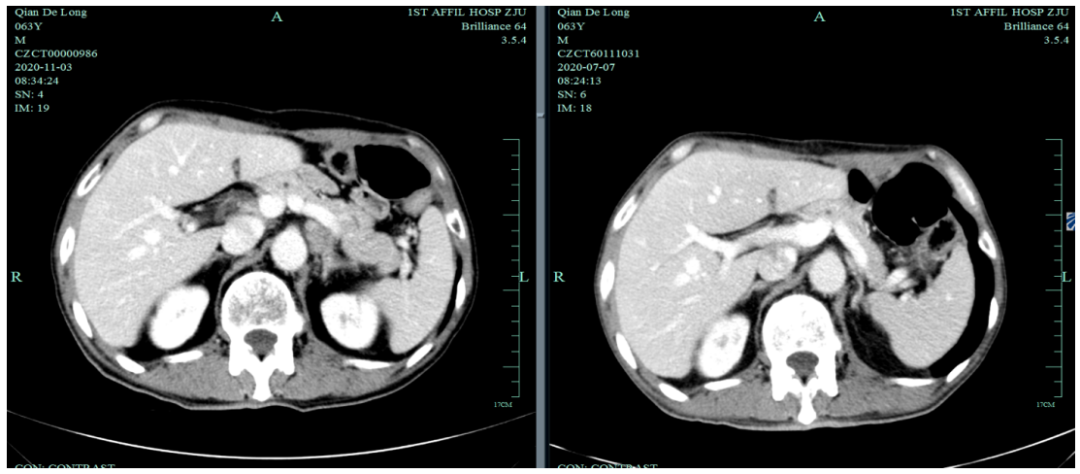

一线化疗疗效评估(2019.6 vs 2019.4):胃癌术后改变。影像评估CR。

影像学评估:胃癌术后改变。持续CR。

2020-11-3全腹部CT平扫+增强提示胃癌术后改变,术周及腹膜后多发肿大淋巴结显示,对照2020-7-7CT淋巴结肿大进展,结合临床疗效评估PD。